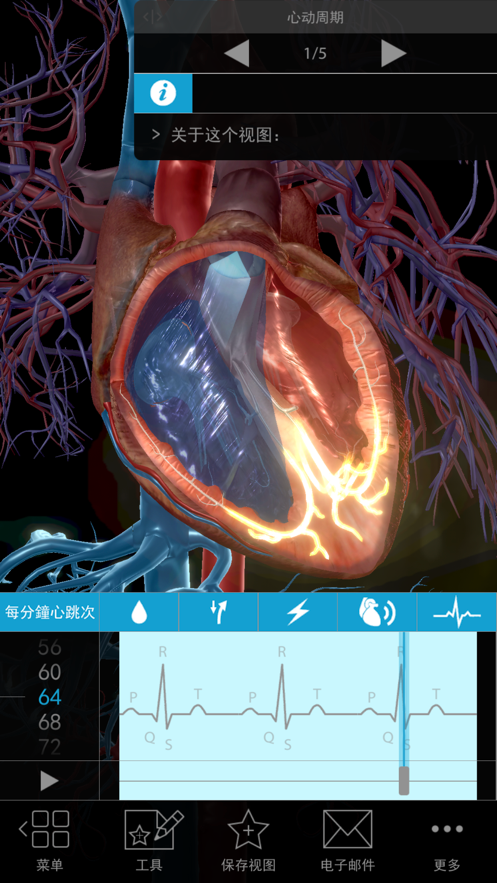

– 设置心率并在可以剖析的跳动三维心脏中直观地观察传导,并在心电图上跟踪